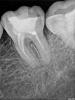

Денис481 Опубликовано 28 июля, 2012 Поделиться Опубликовано 28 июля, 2012 45 зуб протейперами обработал,на снимке перед пломбировкой(справа) все хорошо,а запломбировал чуть не дошел до апекса,как вы думаете грозит зубу что то или нет? просто переживаю как то только начинаю работать хочется чтоб все идеально было как в учебнике,хотя у меня есть во рту зуб который намного хуже пролечен там до апекса не дошли мм 2 но тфу тфу 2 года полет нормальный,а тут я померил 0.4 не дошел.....обидно что канал хороший а так получилось,кстати пломбировал ah+ c гуттой конусной под протейпер Ссылка на комментарий